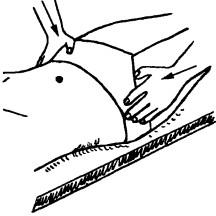

Ábra. 137. Kutatási szimmetrikus elrendezése a csípőlapátból